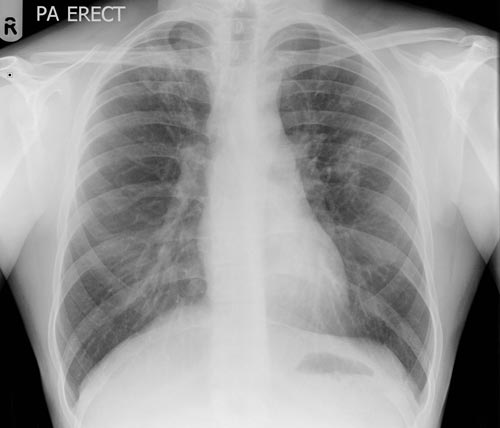

Основные синдромы на рентгенограмме

На рентгенографическом снимке, выполненном в передней проекции, контуры легких образуют легочные поля, по всей площади, пересекаемые симметричными тенями ребер. Крупная тень, между легочными полями образуется совокупным наложением проекции сердца и магистральных артерий. В пределах контура легочных полей, можно увидеть корни легких, расположенные на одном уровне с передними концами 2 и 4 ребер и незначительное затемнение площади, вызываемое богатой сосудистой сетью, располагающейся в ткани легких.